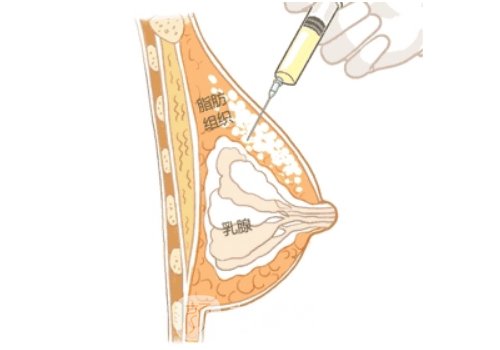

脂肪豐胸:是通過手術(shù)外科的方式��,先在其他部位進行抽脂�����,然后將抽取出來的脂肪提純過濾��,然后再利用針劑注射的方式將脂肪填充到胸部合適的位置�,就可以更好的解決胸部扁平��,讓胸部的形態(tài)看起來更加瑩潤豐滿����。